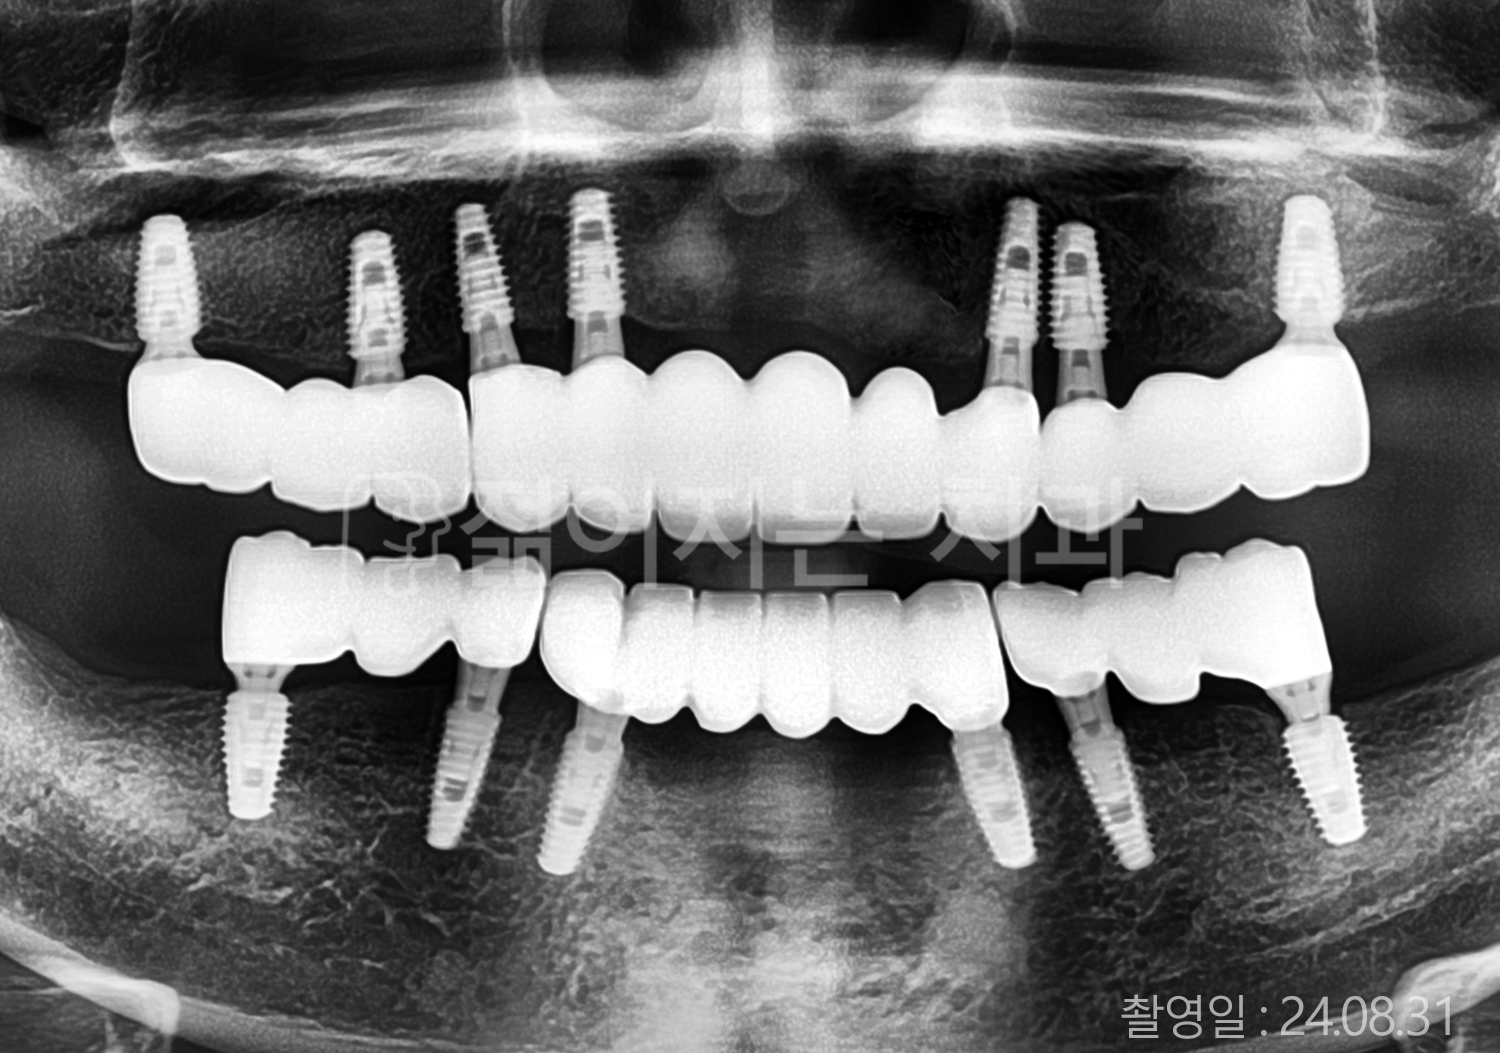

• 70대 고혈압, 고지혈증 전체치아 10개 이상 임플란트

• 60대 당뇨, 간염 전체치아 10개 이상 임플란트

• 80대 골다골증 전체치아 6개 이상 임플란트

• 70대 고혈압, 당뇨 전체치아 10개 이상 임플란트

• 60대 간 질환 전체치아 10개 이상 임플란트

• 60대 전체치아 10개 이상 임플란트

• 70대 전체치아 10개 이상 임플란트

• 50대 전체치아 10개 이상 임플란트

• 60대 고혈압, 고지혈증 전체치아 10개 이상 임플란트

• 40대 고지혈증, 뇌혈관 질환 전체치아 10개 이상 임플란트